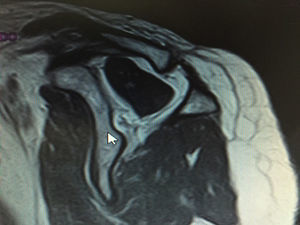

Clasificación de acuerdo con la calidad del tendónLa calidad del tendón se puede evaluar por TC o RM y su función principal es determinar si el tendón, por su calidad, es reparable. La clasificación más usada es la clasificación de Goutallier (tabla 5), basada en la existencia de infiltración grasa en imágenes de TC. Fuchs ha publicado también una clasificación similar con el uso de RM (figs. 3–6).